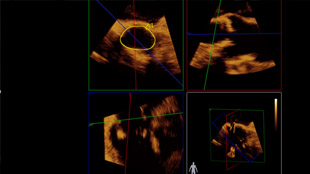

تم تشخيص أحد المرضى لديك بتضيّق في الصمام الأورطي المصحوب بأعراض. يبلغ عمر المريضة 85 عامًا وهي تعاني من السكري وارتفاع ضغط الدم. أنت تدرك خطورة وضعها الصحي ما يجعلها غير مناسبة لجراحة القلب ولكن يسمح لها بأن تكون مرشحة لاستبدال الصمام الأورطي باستخدام القسطرة (TAVR). في يومنا هذا، تمنح حلول التصوير المبتكرة والأجهزة التي تعمل عن طريق الجلد الأمل لبعض المرضى الذين لا تتوفر لهم حتى الآن أي خيارات علاجية أخرى.